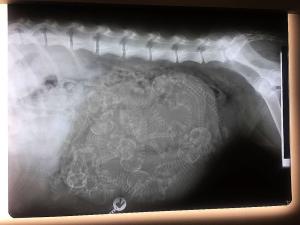

Wir waren mit Haidee zum Welpenzählen.

Das Ergebnis gibt es HIER

Viel Spaß beim zählen :-)